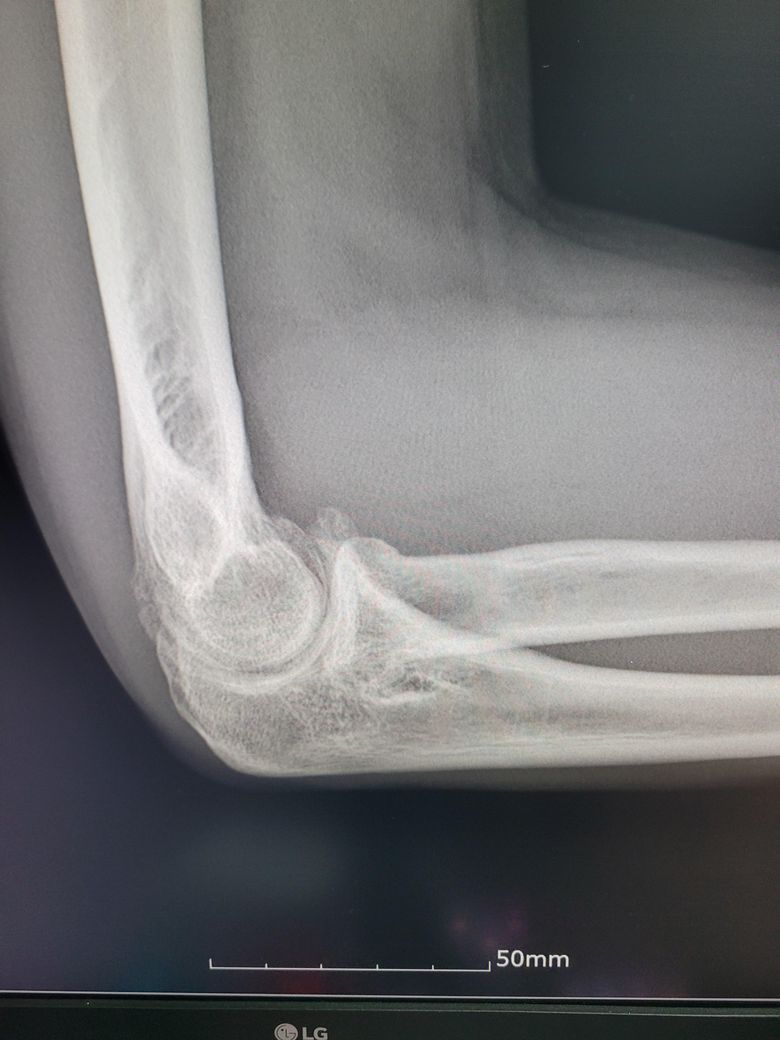

팔이 아파서 여러병원 찾아다니느라 엑스레이 사진도 복사해왔는데 1,2년 전에 비해서 팔꿈치에 동그란 게 생겼더라구여 이게 뭔지 모르겠습니다

과거에 활액막연골종으로 같은 부위를 수술받은 적이 있습니다

• 3번 째 사진

활액막연골종은 일반적으로 엑스레이에서 뼈의 경계가 부풀어 오르거나 변형된 모습이 나타날 수 있습니다.

엑스레이에서 종양은 종종 비정상적인 경계와 불규칙한 모양을 보입니다 뼈의 구조와 혼합된 모습 일 수 있습니다.